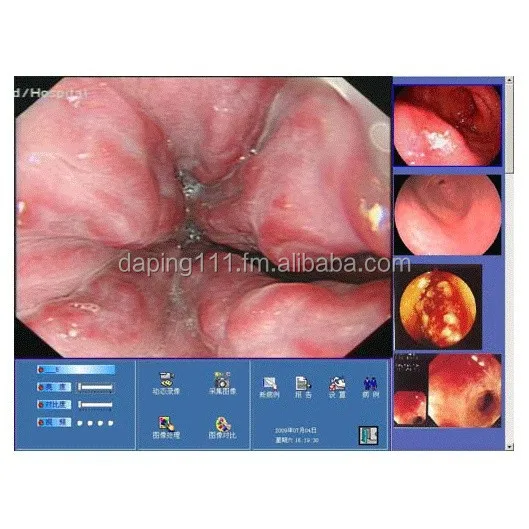

Software Of Endoscope Station

- Category:

- Supplier: MarchCreative,Tech.,Co.,Ltd.,[Liaoning,China]MarchCreative

RUB 45,490.80

In Stock